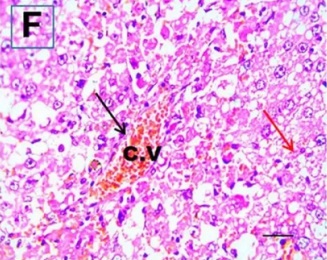

Put the liver tissue section under a microscope, and you can see that cisplatin can cause liver congestion (the blood that should return to the heart is blocked and stagnates in the hepatic veins), cell degeneration (vacuoles appear, which is the earliest change in cellular injury), apoptosis and necrosis, but these conditions can also be alleviated by using Ganoderma lucidum.

Figure 2 Effects of cisplatin and Ganoderma lucidum on hepatocytes